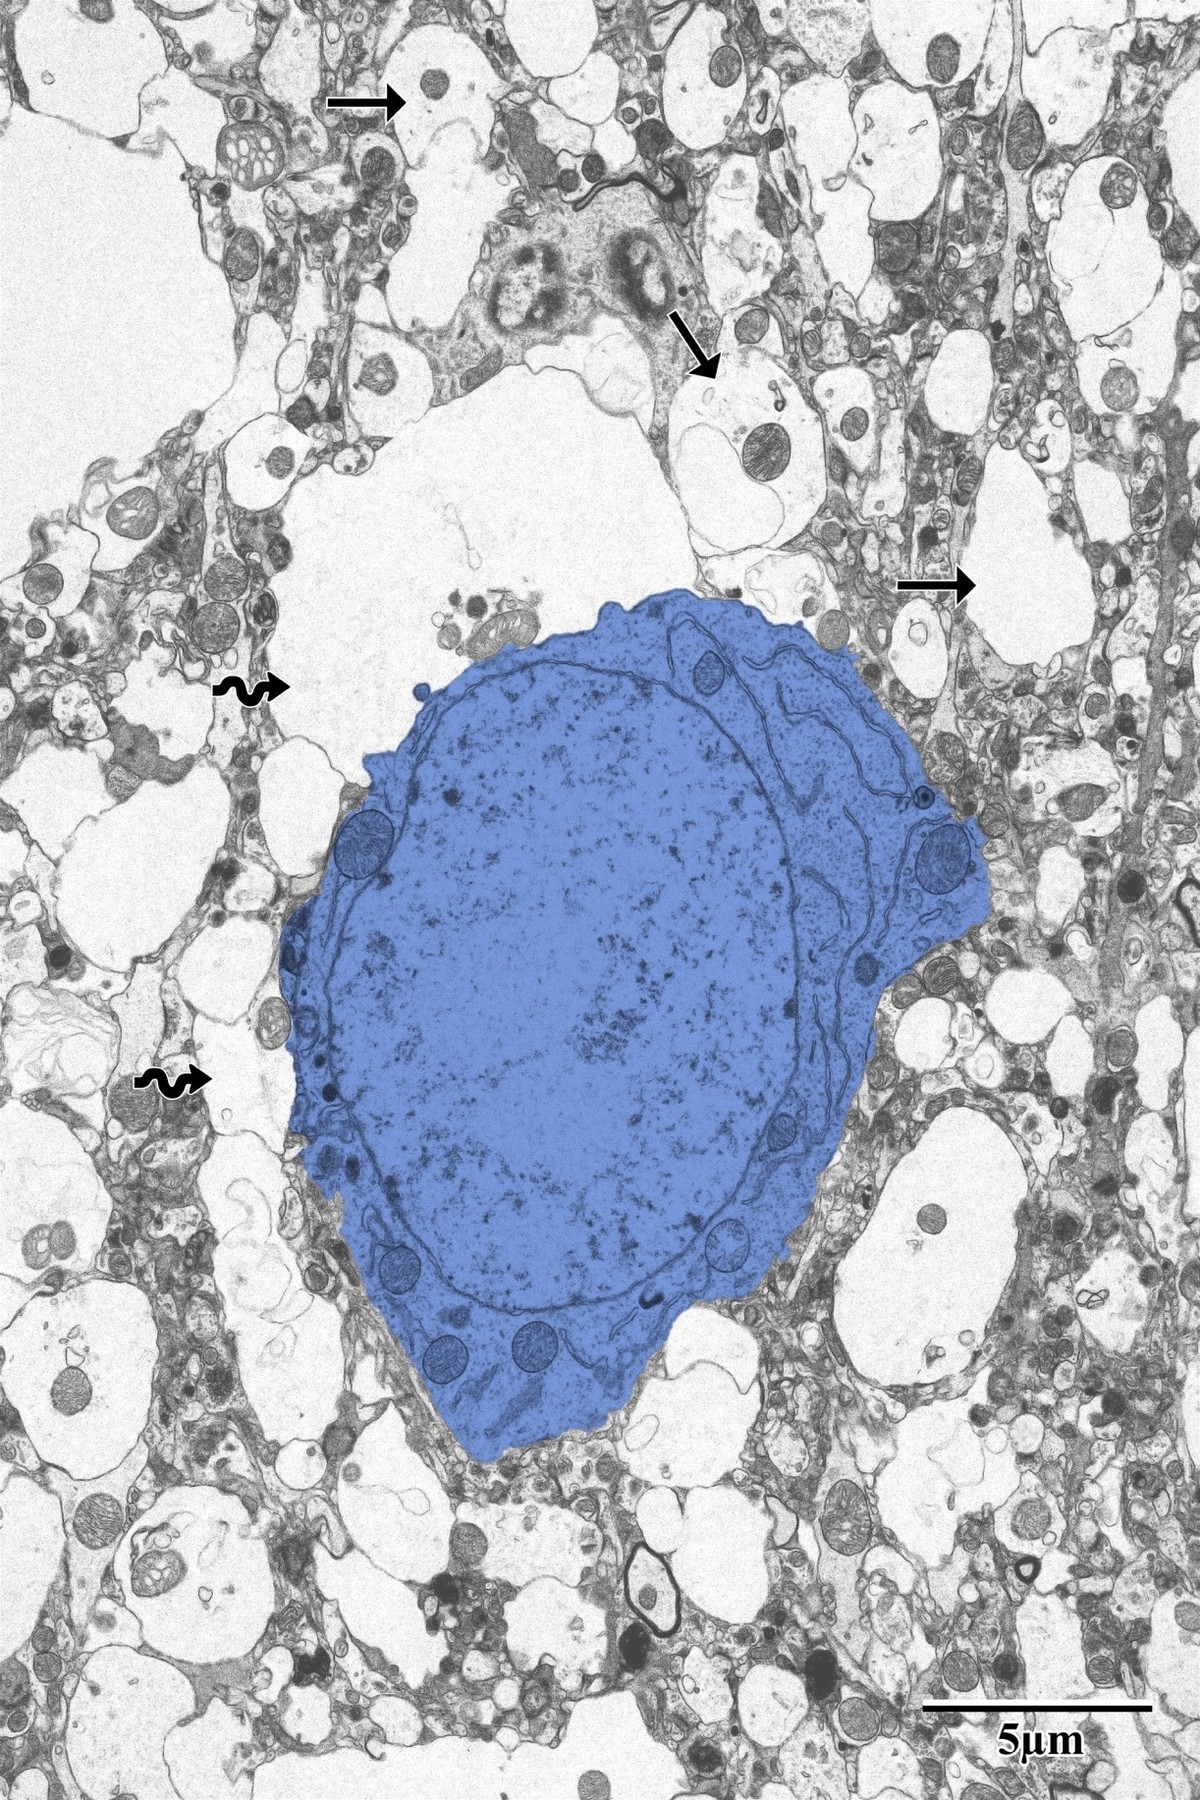

Necrotic Core & Infarct Zone

Within the necrotic core, neurons show complete loss of organellar integrity — barren dendritic processes, no identifiable synapses, and pyknotic glial cell nuclei. This zone is characterized by widespread degenerating neuropil tissue and the complete absence of functional synaptic structures.

Degenerating neuron and pyknotic glial cell in the necrotic core

Necrotic core: degenerating neuron (blue) and pyknotic glial cell (arrow) surrounded by disintegrating neuropil. No identifiable synapses were observed within this region. Scale bar: 5 µm. From Bayati, BSc Honours Thesis 2018.